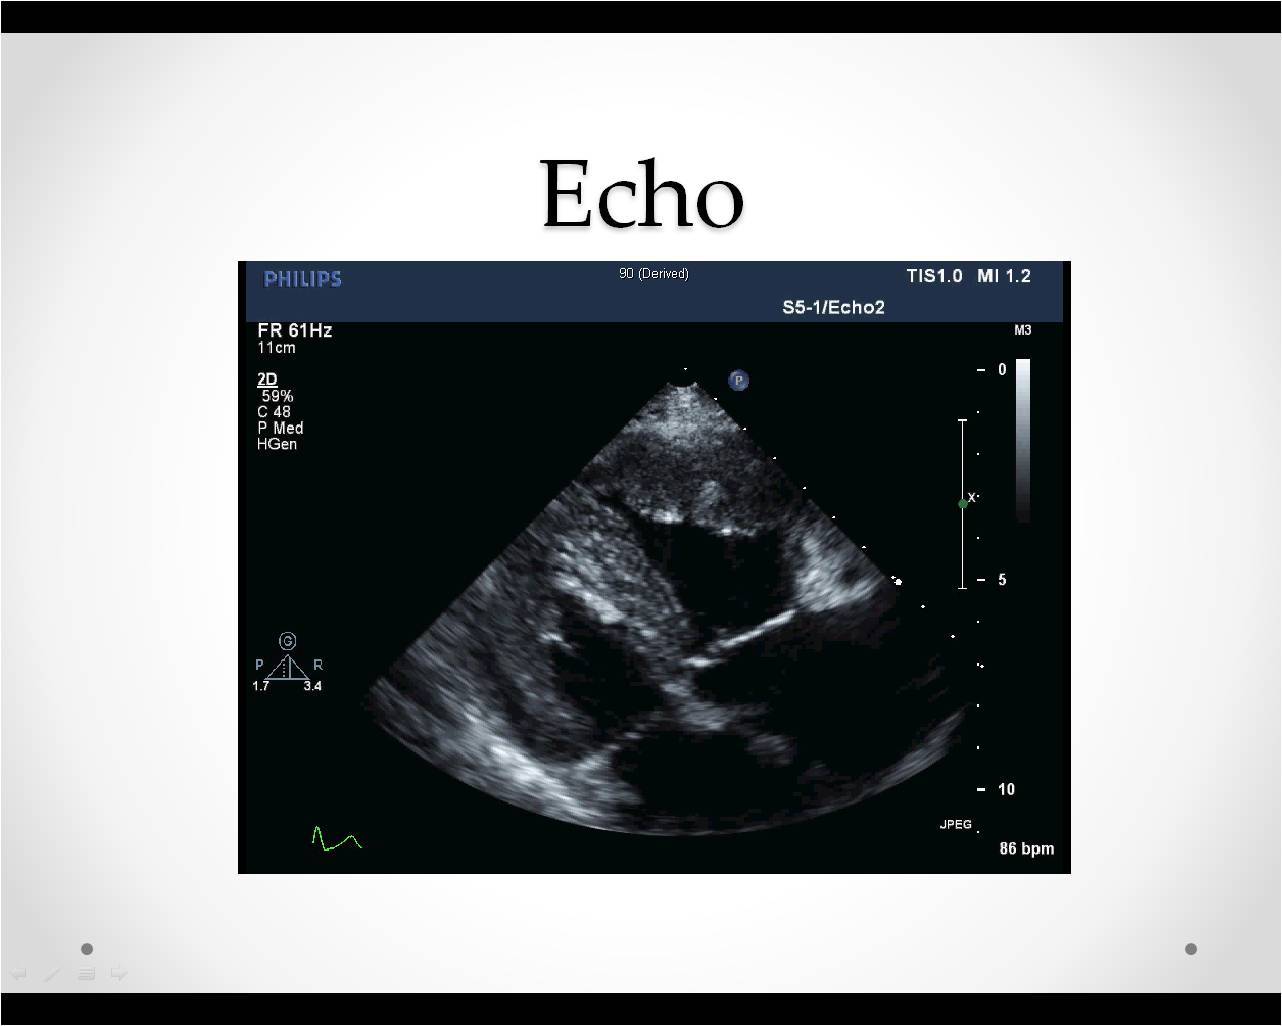

Abnormal finding on echocardiography

Kyungsun Nam, Department of Radiology, Yonsei University College of Medicine

HIT : 15